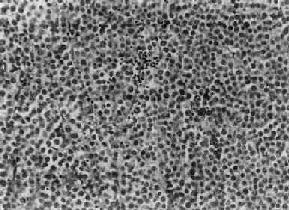

肉眼观,睾丸肿大,有时可达正常体积的10倍,少数病例睾丸大小正常。肿瘤体积大小不一,小者仅数毫米,大者可达十余厘米,通常直径为3~5cm。由于睾丸白膜比较韧厚,未被肿瘤破坏,故通常睾丸的原来轮廓尚保存。切面瘤组织呈淡黄或灰黄色,实体性,均匀一致如鱼肉,其中往往可见到不规则坏死区。镜下,典型的精原细胞瘤有瘤细胞形态结构单一和间质内有淋巴细胞浸润两个特征,(图14-1)。瘤细胞弥漫分布或呈索状结构,细胞的形态一致,与正常精小管内精原细胞相似,瘤细胞大,圆形或多角形、境界清楚、胞浆透明,核大、位于中央,核膜及染色质较粗,有1~2个嗜酸性核仁,核分裂像不多见。间质为纤细的纤维组织或致密的胶原纤维,其中有多少不等的淋巴细胞浸润,有时可有淋巴滤泡形成。

图14-1 精原细胞瘤

瘤细胞大、胞浆透明,核大,核仁明显,间质内有淋巴细胞浸润